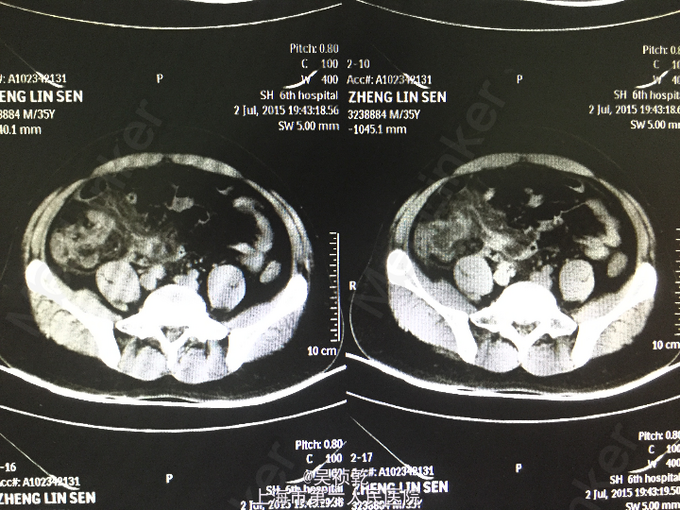

患者男性,35岁。因“右下腹疼痛1天,伴恶心、呕吐”入院。患者1个月前无明显诱因下脐周疼痛,后转移至右下腹,疼痛固定。无恶心呕吐,无头晕乏力。于外院拟尿路感染治疗,补液消炎1周后症状缓解。昨日下午,右下腹疼痛加剧,伴发热,体温约38.2摄氏度,有恶心,呕吐症状。故来我院治疗,完善各项检查,查腹部CT;阑尾形态增粗伴阑尾壁肿胀,回盲部及阑尾周围可见大量渗出,前列腺密度均匀,未见明显增大,两侧精囊未见明显异常,膀胱充盈可,盆腔未见明显肿大淋巴结,盆腔未见明显积液,。为进一步治疗收住入院。患者自起病以来,精神可,胃纳差,大便如常,小便如常,体重未见明显下降,睡眠一般。

查体:腹部平坦,无胃肠型。腹壁柔软,有压痛,位于右下腹,伴反跳痛,无腹部包块,振水音阴性,未触及肝;未触及脾 ,无移动性浊音,肝区无叩痛。肠鸣音正常。结肠充气试验:阴性;腰大肌试验:阴性;闭孔内肌试验:阴性。 辅查:2015-7-3 生化检验报告:血清钠(干式) 136 mmol/L ↓,总蛋白(干式) 60 g/L ↓,白蛋白(干式) 32 g/L ↓,谷草转氨酶(干式) 14 U/L ↓,总胆红素(干式) 62 μmol/L ↑。 血常规检验报告:白细胞 14.3 X10^9/L ↑,红细胞 5.18 X10^12/L ,淋巴细胞百分比 9.5 % ↓,嗜酸性细胞百分比 0.1 % ↓,中性细胞百分比 84.8 % ↑,嗜酸性细胞绝对值 0.01 X10^9L ↓,单核细胞绝对值 0.8 X10^9L ↑,中性细胞绝对值 12.1 X10^9L 腹部CT:阑尾形态增粗伴阑尾壁肿胀,回盲部及阑尾周围可见大量渗出,前列腺密度均匀,未见明显增大,两侧精囊未见明显异常,膀胱充盈可,盆腔未见明显肿大淋巴结,盆腔未见明显积液,。

患者入院诊断:急性阑尾炎,入院后本准备急诊手术,但患者家属坚决要求保守治疗,故予保守治疗,但患者第二天腹痛症状及体征没有缓解,且出现高热伴巩膜轻度黄染,诊断为:急性阑尾炎伴周围大量渗出,同时合并门静脉炎,故于第二天行阑尾切除术,术中见腹腔内渗出液100ml(脓液),有臭味。阑尾长10cm,粗直径1cm,阑尾有坏疽,多处穿孔,根部坏疽穿孔,阑尾与小肠粘连,阑尾为回肠后位。分离粘连,结扎处理阑尾系膜,于阑尾根部切下阑尾,阑尾根部之回盲部行间断缝合修补 残端闭合方式 。探查回盲部及升结肠根部10cm,回肠末端30cm,未见其他病变。 于回盲部修补处放置双套管一根,盆腔放置负吸球一根,清点纱布及器械无误,逐层关闭切口,切口留置皮片引流。术后诊断:急性阑尾炎伴坏疽穿孔,术后予抗炎等对症支持治疗,术后仍有反复发热,术后3天体温消失,术后一周恢复出院。